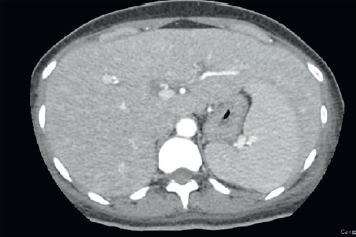

Ragazza di 30 anni, forte fumatrice, 1 pacchetto/die da 15 anni, giunta in Pronto Soccorso presso l’Ospedale di Carate Brianza per iperpiressia negli ultimi dieci giorni senza localizzazione d’organo. Durante la degenza in Medicina riferita piressia con associata artromialgia al cingolo pelvico. Agli esami ematici d’ingresso PCR 7,8 mg/dL, potassio 2,9 mEq/L, sodio 131 mEq/L, PLT 95 · 103/μl, ALT 75 U/L, AST 132 U/L, all’Rx torace riscontro di rinforzo dell’interstizio. All’ecocardiogramma modesta falda di versamento pericardico. Durante la degenza a seguito del peggioramento dell’addominalgia la paziente è stata sottoposta a ecografia addominale, visita chirurgica e ginecologica negativi per acuzie. Successivamente, per il peggiorare degli scambi respiratori e delle condizioni cliniche, è stata eseguita una TC torace e addome con evidenza alla TC torace di quadro a vetro smerigliato agli apici polmonari, soprattutto a destra e al lobo medio, e versamento pleurico bilaterale (Figure 1, 2). Alla TC addome ingrossamento del lobo sx epatico (Figura 3) con diffuso ispessimento del colon ascendente sino al colon trasverso e discreto versamento nello scavo pelvico. Agli esami ematici si è assistito ad un progressivo incremento dei globuli bianchi 12,2 · 103/mm3 con linfocitosi 68%, rapporto CD4/CD8 0,19 (segnalate forme immature granulocitarie e linfociti attivati).

Figura 3.TC addome: ingrossamento del lobo sn epatico.